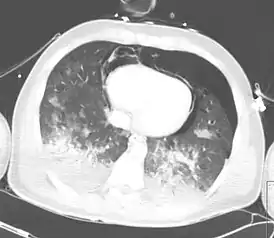

Наряду с травматическим двухсторонним гемопневмотораксом, пневмоперикардом и пневмомедиастинумом, визуализируются распространённые зоны консолидации в нижних долях обоих лёгких, обусловленные контузией. | |

При консолидации плотность лёгочной ткани повышается вплоть до мягкотканной, печёночной. Клинически консолидация проявляется ограничением подвижности грудной клетки на стороне поражения, усиленным голосовым дрожанием, притуплением перкуторного звука, бронхиальным дыханием[2]. При радиологических исследованиях (рентгенографии, компьютерной томографии) лёгочная консолидация представляет собой участки, непроницаемые для рентгеновских лучей, на фоне которых не прослеживается сосудистый рисунок лёгочной ткани (в отличие от менее выраженного снижения воздушности по типу «матового стекла»). Консолидация наиболее типична для сформировавшейся зоны пневмонии, встречается при интерстициальных заболеваниях лёгочной ткани.